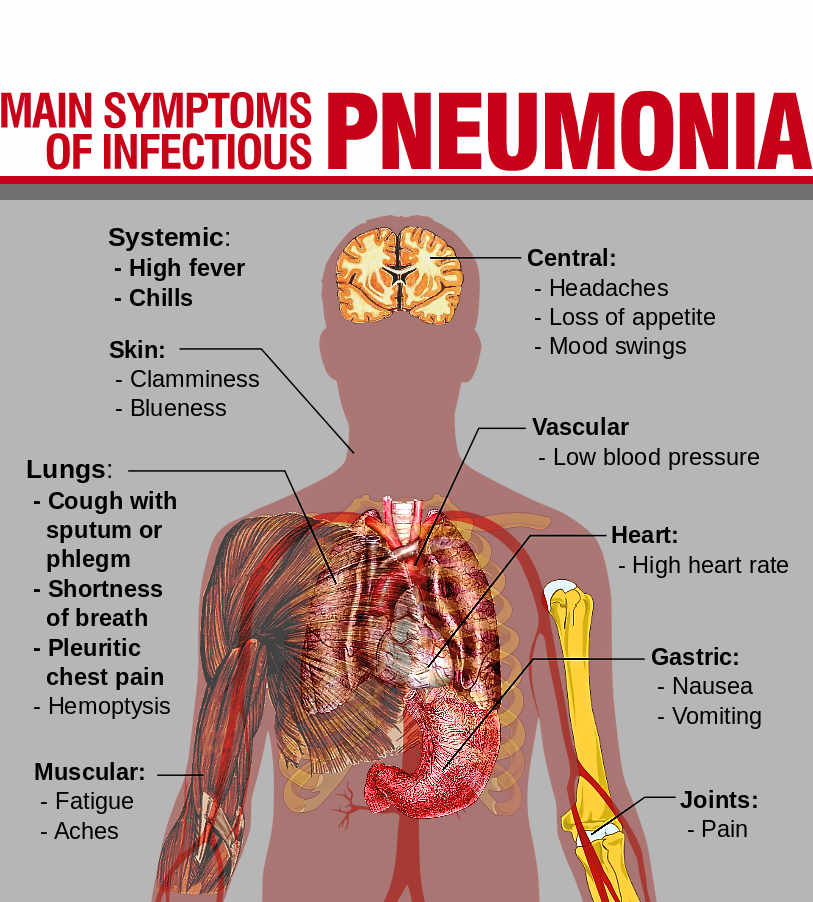

1. Pneumonia:

The air sacs of the lungs are clogged up with mucus making gaseous exchange difficult. It is caused bacteria present in an unhealthy, cold and wet environment. Sufferers experience pains on the chest and difficulty in breathing.

1. Pneumonia:

The air sacs of the lungs are clogged up with mucus making gaseous exchange difficult. It is caused bacteria present in an unhealthy, cold and wet environment. Sufferers experience pains on the chest and difficulty in breathing.